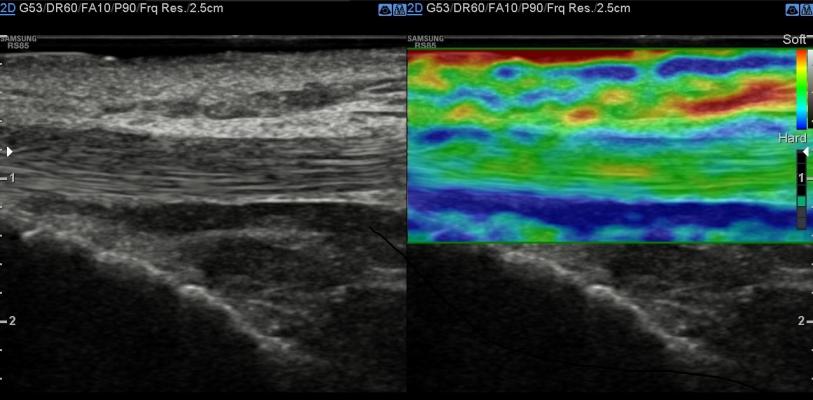

The RS85A S-Shearwave Imaging provides new indicators for clinical diagnosis by quantifying the elasticity of tissue or lesions via shearwave elastography. Photo courtesy of Business Wire.

- S-Shearwave Imaging: Provides new indicators for clinical diagnosis by quantifying the elasticity of tissue or lesions via shearwave elastography, which may help increase the accuracy of diagnosis for breast and liver diseases;